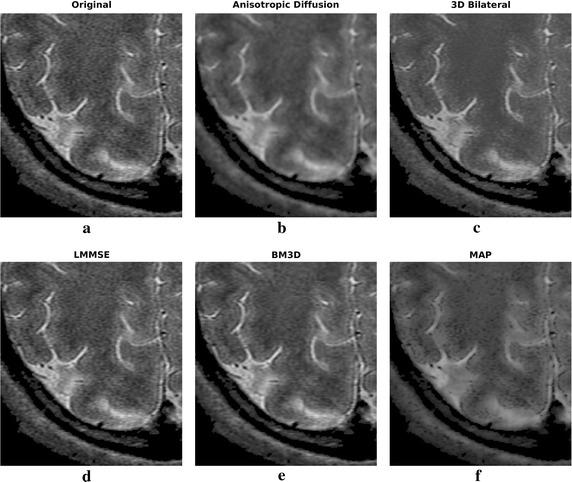

The method exploits Markov random fields in order to implement a 3D maximum a posteriori estimator of the image. Due to the local nature of the considered model, the algorithm is able do adapt the smoothing intensity to the local characteristics of the images by analyzing the 3D neighborhood of each voxel. The effect is a combination of details preservation and noise reduction. The algorithm has been compared to other widely adopted denoising methodologies in MRI. Both simulated and real datasets have been considered for validation. Real datasets have been acquired at 1.5 and 3 T. The methodology is able to provide interesting results both in terms of noise reduction and edge preservation without any supervision.

该方法利用马尔可夫随机场来实现图像的三维最大后验估计器。由于所考虑模型的局部性质,该算法能够通过分析每个体素的三维邻域,使平滑强度适应图像的局部特征。效果是细节保留和降噪的结合。该算法已与MRI中其他广泛采用的去噪方法进行了比较。模拟数据集和真实数据集均已用于验证。真实数据集是在1.5T和3T下采集的。该方法能够在无需任何监督的情况下,在降噪和边缘保留方面提供有趣的结果。